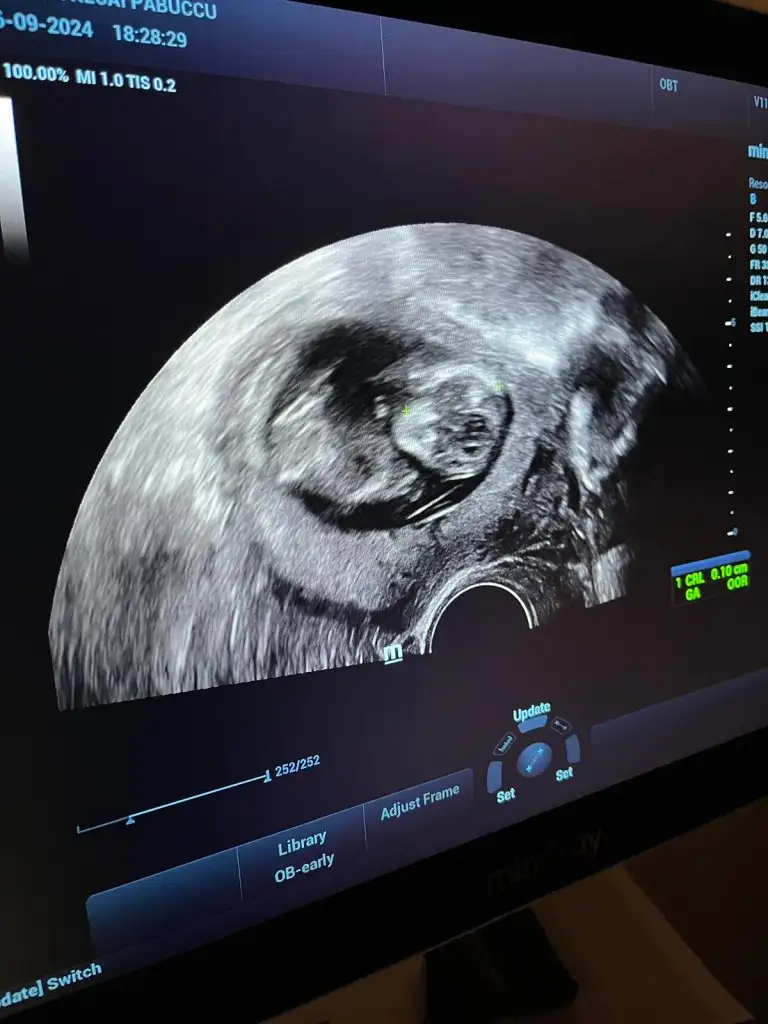

12 haftalık cinsiyeti belli oldu

Kızlar doktorum 13. Haftamda kız dedi kesin bir şekilde sizce de erken değil mi kesin konuşması kafam karıştı sızce cınsıyet nedır tahmın eder mısınız